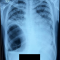

Mohon masukan dan sarannya, kalau ada pasien berobat yang baru membawa hasil test lab HIV positif dan juga membawa hasil pemeriksaan TB paru aktif (dengan hasil BTA dan Rontgen (+)), apakah harus langsung memulai terapi ARV secepatnya atau mengobati TBnya dulu dan ARVnya ditunda? kalau ya, berapa lama bisa menunda ARVnya? Apa ada alur penatalaksaanaan yang khusus untuk kasus seperti ini?